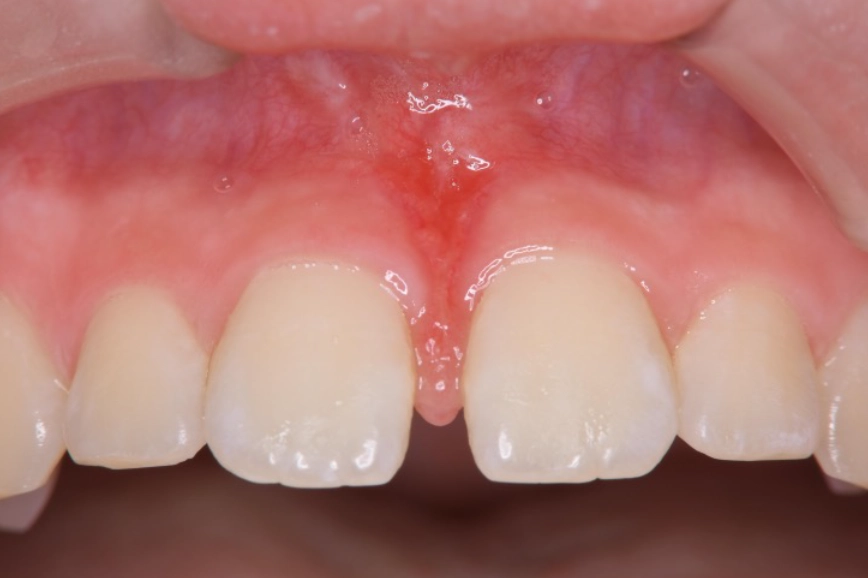

マウスピース矯正の症例

治療前

治療中

治療後

| 治療名 | 上唇小帯切除術、 アライナー矯正治療 |

| 患者様情報 | 10代 女性 |

| 担当医 | 高橋 隼平 先生 |

| 費用 | 800,000円 (税込) |

| 主訴 | 見た目が気になっている。上の前歯は歯ブラシが当たると少し痛い。 |

| 治療期間 | 約1年6ヶ月 (約2~3ヶ月に 1回ペース) |

| 治療内容 | 見た目が気になり、上の前歯は歯ブラシが当たると少し痛いとのことで来院されました。 上唇小帯については、上唇小帯切除術し、傷口が治癒した後は、インビザラインにて矯正治療を行いました。 |

| 治療のリスク | 矯正治療後、保定装置をしっかり使わないと後戻りする可能性があります。 |